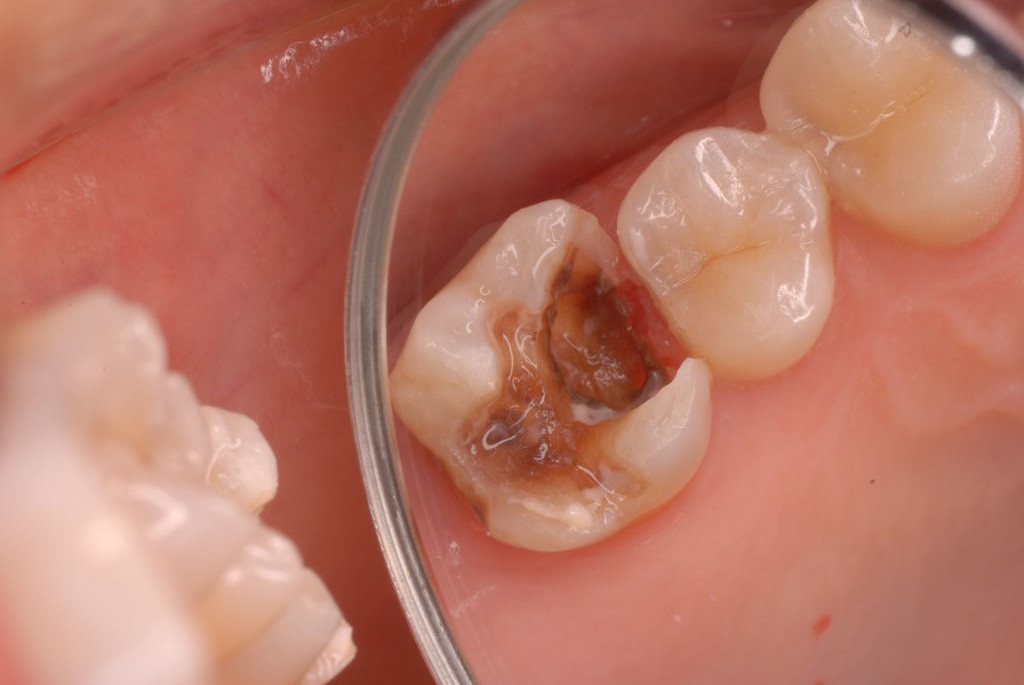

入れ歯の話から入りました。色々不満で注文があるようです。でも話が一段落して口腔内を調べると殆どの歯が重症で抜けそうな歯だらけなのです。

なぜ病気になるのかわからない方が多すぎます。歯が抜けるのは病気だからです。病気を治さずに何かお口の中に入れても土台である歯が抜けてしまっては同じことなのです。

何故歯が悪くなるのか、歯周病で抜けるのか分からなければ何を入れても歯は悪くなり抜けていくのです。

病気を治しましょう。それから差し歯や入れ歯を入れましょう!物を入れれば入れるほど、磨き方や掃除の仕方が上手にならなければ、すぐ抜けてくるのです。